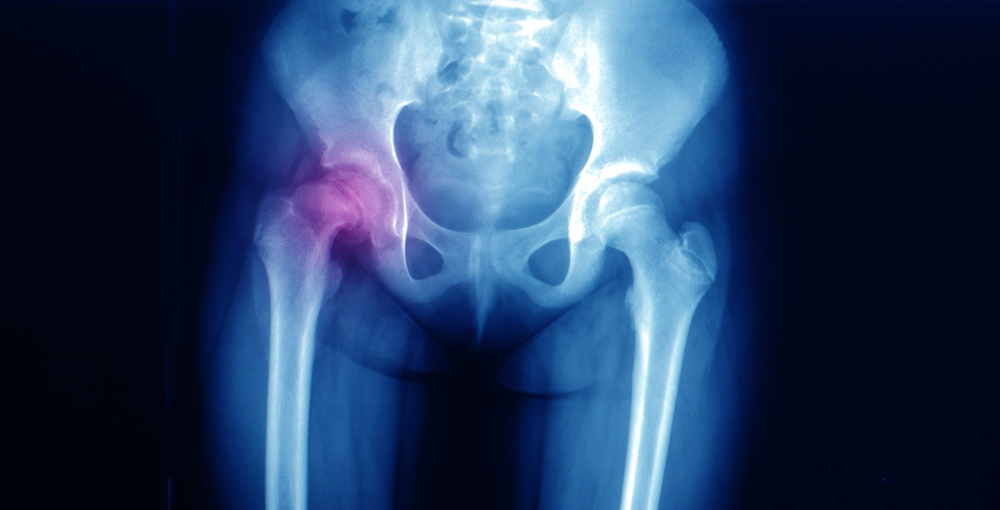

A epifisiólise é o deslocamento da cabeça do fêmur, localizada na região do quadril. Ou seja, o topo (bola) da cabeça do fêmur escorrega além do colo do osso e caminha para trás, causando muita dor. A condição não é tão popular e, por isso, pode acabar não tendo o diagnóstico e tratamento correto.

Além disso, o médico também pode solicitar um exame de raio-X da bacia, tomografia ou ressonância magnética. Exames de sangue para avaliar níveis de hormônios da tireoide também estão inclusos.